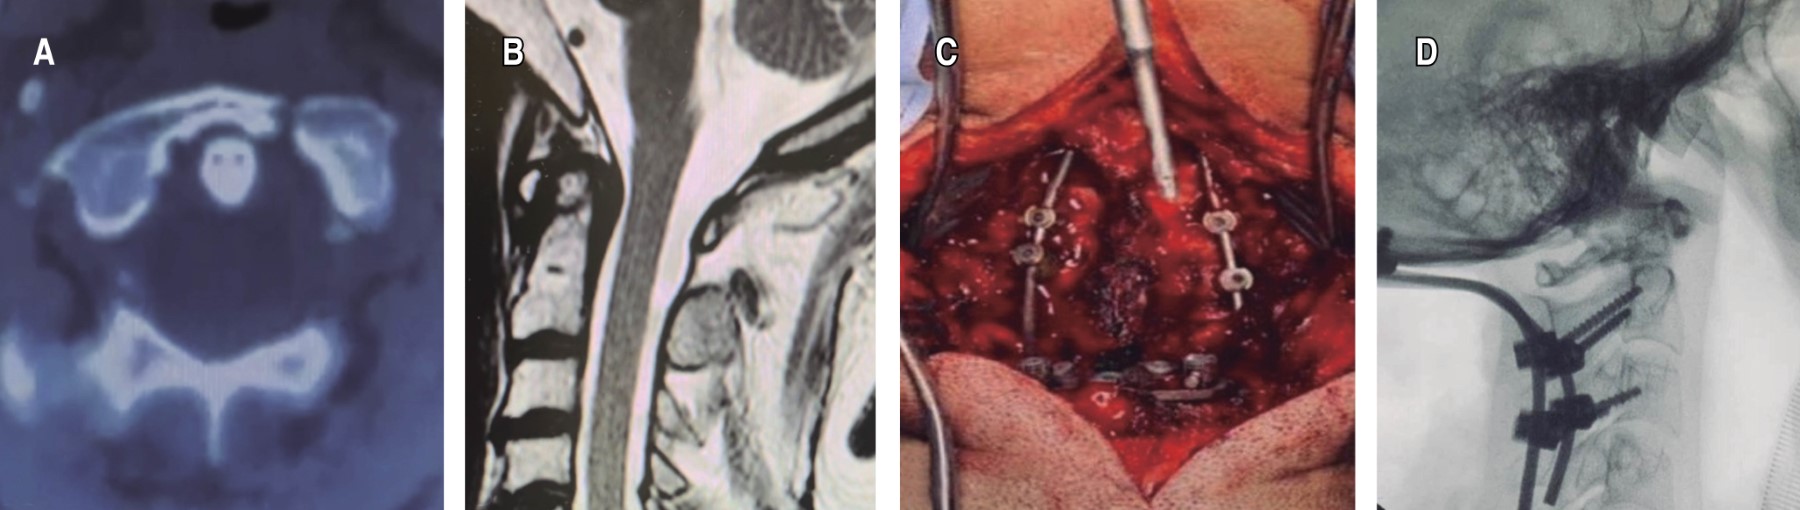

Occipito cervical fixation: report of two cases, clinical and functional results in traumatic cranio cervical instability

Craniocervical junction instability can develop due to congenital, inflammatory, degenerative, traumatic, neoplasms and those following surgical procedures. Occipito-cervical fixation is a demanding technique, but it can be successfully performed with ample knowledge of the anatomy of the region and considering the different options for stabilization of the cranio-cervical junction. Multiple case series have presented adequate stability and fusion of this region with different fixation options, however, the associated cervical pain and limitation of movement in this region has been an important factor for the quality of life of patients. We present two cases of patients with traumatic pathology of the cranio-cervical junction by means of occipito-cervical stabilization with trans-articular cervical screws and occipital plate, evaluating the clinical results by means of pain reduction according to the visual analogue scale (VAS) and functional results according to the modified PROLO scale. The occipito-cervical fixation provided adequate stability, good clinical and functional results with a tolerable range of mobility for activities of daily living.

Figure 1

Figure 2